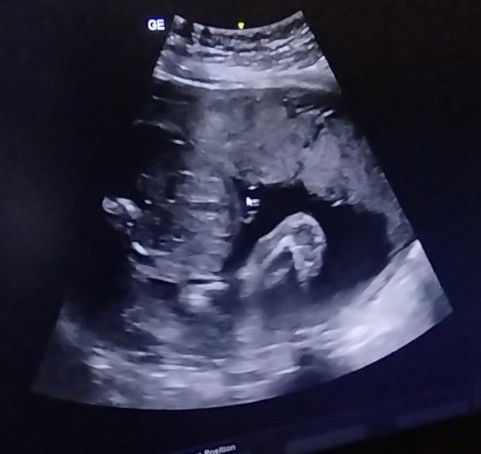

Nak tanya kalau macam ni boy atau girl ye?

Yang berpengalaman bagitau ye...#share